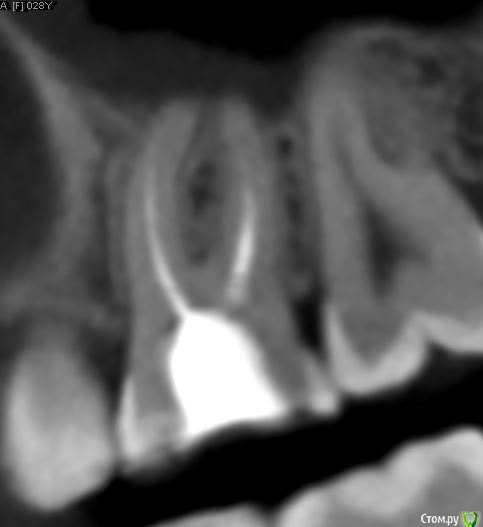

dmitrib81 Опубликовано 19 февраля, 2020 Поделиться Опубликовано 19 февраля, 2020 Помогите определить источник боли в зубе Ссылка на комментарий

krokomot Опубликовано 19 февраля, 2020 Поделиться Опубликовано 19 февраля, 2020 в медиальном корне недопломбировка и наличие вероятно 4ого канала. Ссылка на комментарий

dmitrib81 Опубликовано 20 февраля, 2020 Автор Поделиться Опубликовано 20 февраля, 2020 Зуб делали много лет назад. Примерно неделю назад появились периодические боли, бывает целый день не болит, потом снова ноющая боль. С приёмом пищи никак не связано. На горячие и холод реакции нетПодскажите, может ещё прислать фоток из КТ Пикассо, а то я в этом ничего не понимаю, просто разных фото экрана прислал, без какого-либо понимания, на что смотреть.. Ссылка на комментарий